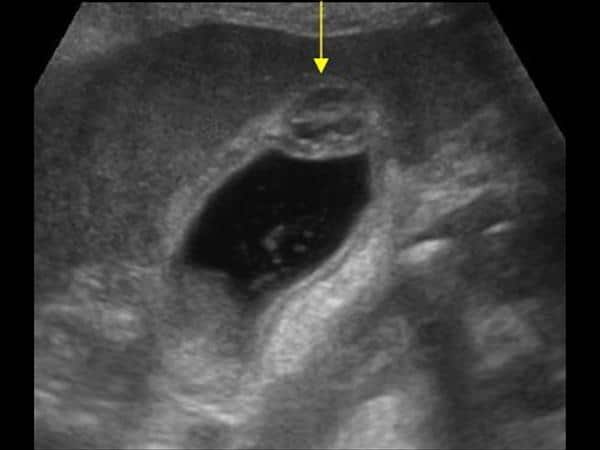

Υπερηχογράφημα άνω κοιλίας

Το υπερηχογράφημα είναι η εξέταση εκλογής:

Τυπικά ευρήματα:

• Πάχυνση του τοιχώματος της χοληδόχου κύστης

• Μικρές ενδοτοιχωματικές κύστεις (Rokitansky–Aschoff κολπώματα)

• Χαρακτηριστικά “comet-tail” ή “ring-down” artifacts πίσω από μικροκυστικές εστίες (αντιπροσωπεύουν κρυστάλλους χοληστερόλης μέσα στα RAS)

• Διάκριση μεταξύ εντοπισμένης, τμηματικής και διάχυτης μορφής ανάλογα με την έκταση της πάχυνσης.

Η παρουσία τυπικών comet-tail artifacts μέσα σε παχύ, αλλά ομαλό τοίχωμα χοληδόχου κύστης είναι σχεδόν παθογνωμονική για αδενομυωμάτωση.